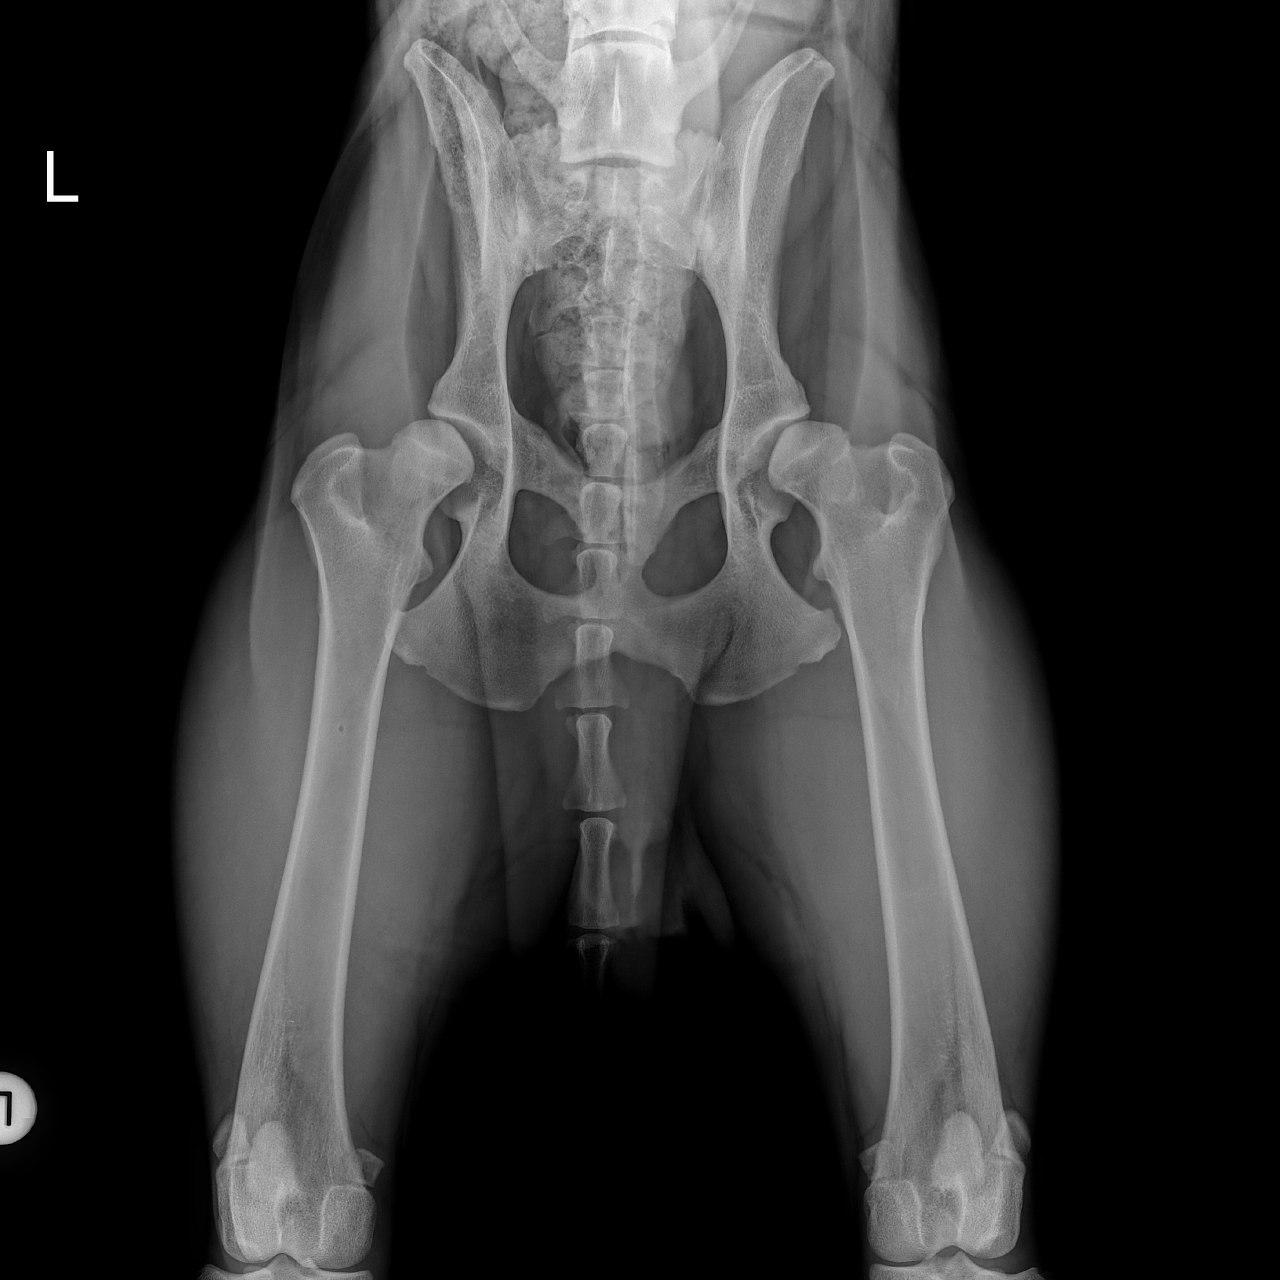

Mit der HD ist das so ne Sache..... die Vererbung spielt eine sehr große Rolle, ja. Aber bei unserer Peggy Zb ist es so, dass mehrere Generationen nachweislich HD und ED frei sind und auch frei von Spondylosen. Als einziger Hund überhaupt in der gesamten Zucht hat unsere Dame alles mitgenommen, was zu kriegen war;(: sie hat nicht nur schwere HD, weil ihre Hüfte viel zu locker ist, sondern dadurch bedingt am rechten Knie bereits schwere Arthrose und hinten links eine Sehenschwäche (durch Überlastung), weshalb sie dort durchtrittig ist. Und als würde das alles nicht schon vollkommen reichen, wurden aktuell auch noch mehrere heftige Spondylosen diagnostiziert;(. An einer Stelle ist sogar schon etwas abgebrochen8|.